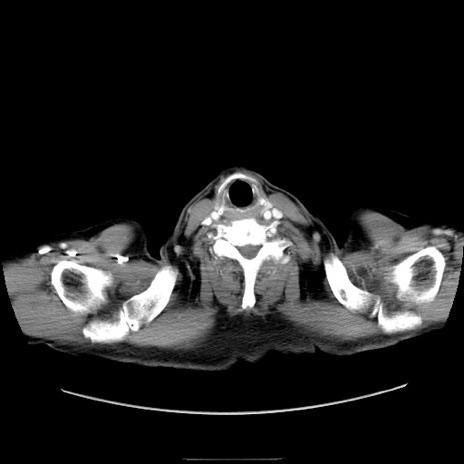

症例30(横断像)

【症例】80歳代男性

【主訴】臍周囲痛

【現病歴】約6時間前から臍下部痛が出現。次第に腹部膨隆・背部痛も生じてきたため来院。背部痛の場所は変化しない。

【身体所見】意識清明、BT 36.3℃、BP  131/87mmHg、P 87bpm、SpO2 100%(RA)、臍周囲自発痛・圧痛あり、反跳痛なし、自発痛部位に一致して板状硬あり、腹部膨隆、腸雑音減弱、CVA tenderness両側陰性。

【データ】WBC 19600、CRP 0.33